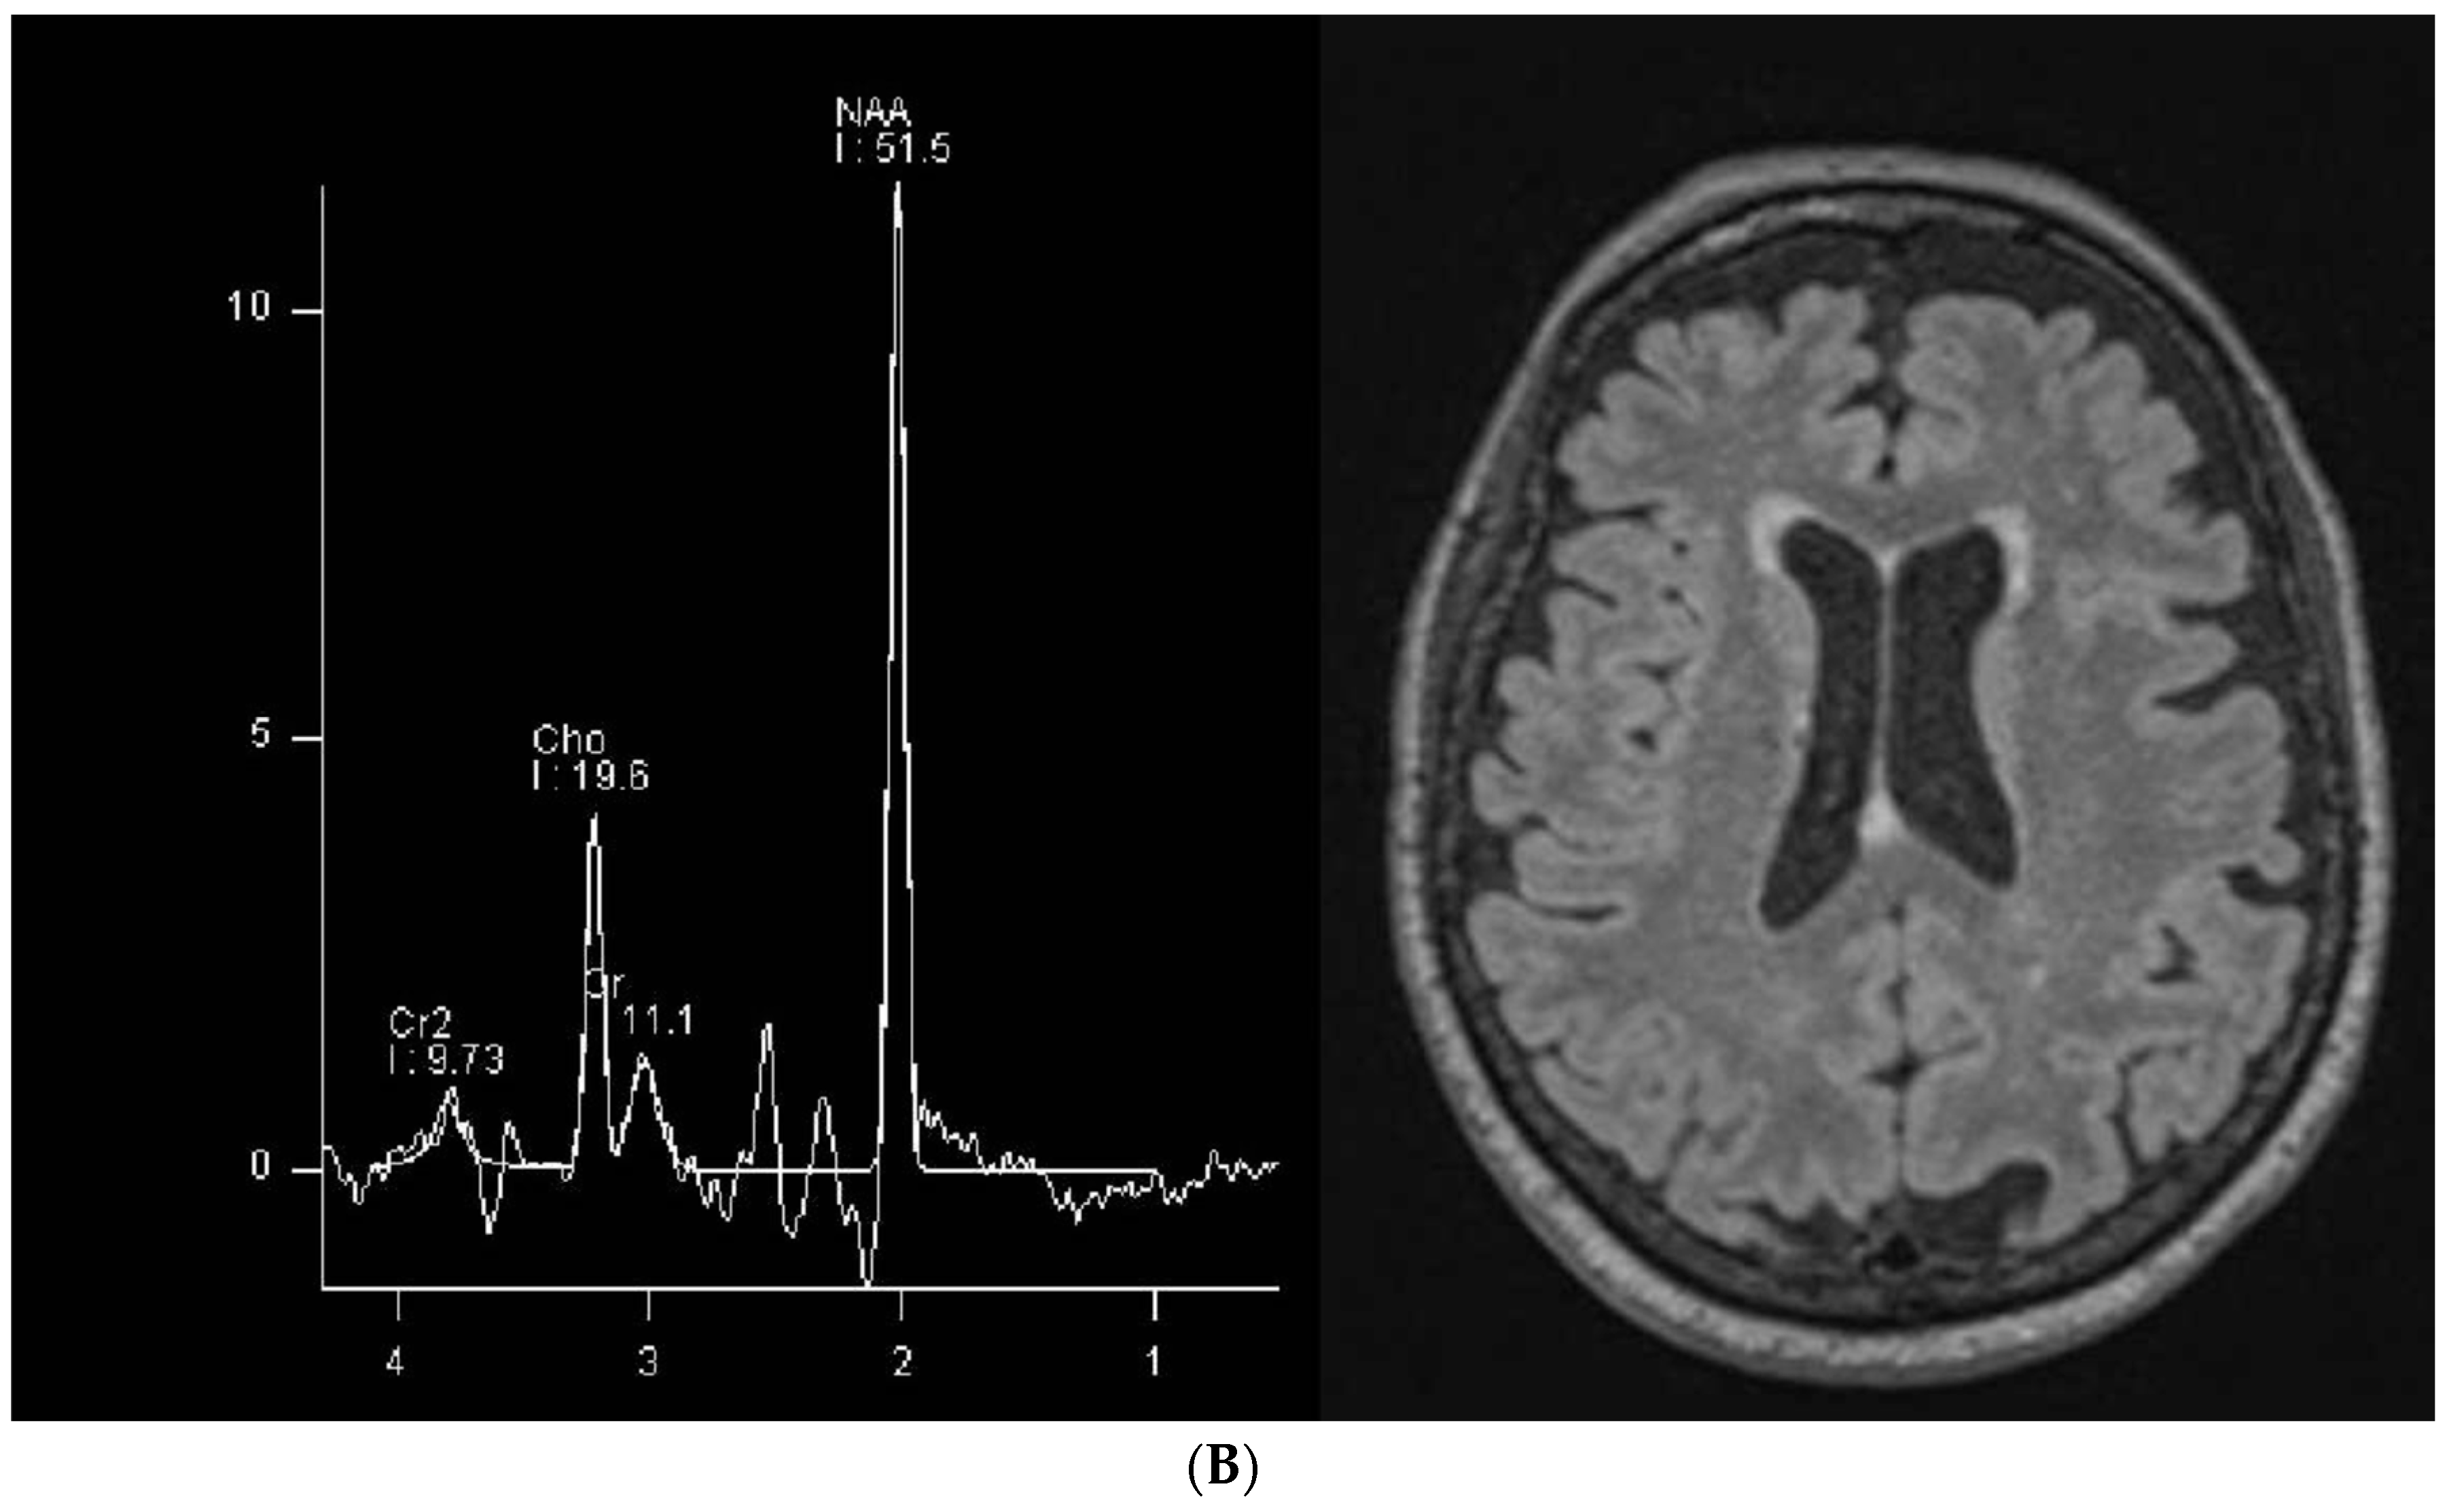

| Social environment | He lived with his family at the time of this investigation; he had to be admitted to institutional care shortly afterwards upon the death of his grandmother who cared for him. | He lived with his family, and he still does so. |

| Speech | He only speaks a few words with semantic meanings; verbal understanding is spared. | Some difficulty in finding words but information is conveyed and his vocabulary has a fair amount of complexity. |

| Cognitive state | Severe cognitive impairment, lack of attention with only occasional collaboration; he is often agitated, especially in unfamiliar situations. | Cognitive impairment but he shows a fair amount of attention and concentration; behavior is not grossly abnormal. |

| Seizures | Seizures in the past, not in the past two years. | Seizures up to the age of 6, but no seizures since then. |

| Neurological examination | No focal lesion signs, global motor impairment, fatuity, hyperkinesia, mild axial hypotonia, internal rotation of the feet. Right hand dominance. | Normal neurological examination except for slight impairment in fine motor movements of the hand fingers, bilaterally. Right hand dominance. |